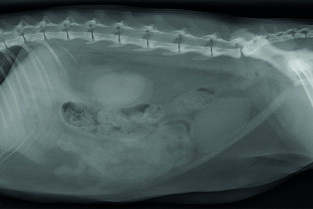

Après le vif succès de la soirée de mai 2018 consacrée à la radiographie thoracique, le bureau du groupe Île-de-France de l’AFVAC a le très grand plaisir d’accueillir le 22 mai 2019, nos confrères Juliette BESSO et Yannick RUEL pour une soirée unique consacrée à la radiographie abdominale.

Avec l’essor de l’échographie comme mode d’exploration des maladies de l’abdomen, la radiographie abdominale a vu son champ d’application se réduire progressivement. Pourtant, le diagnostic de certaines affections abdominales peut être aisément évoqué ou établi par radiographie à condition de connaître et savoir reconnaître les signes clé.

Juliette BESSO et Yannick RUEL nous proposerons de revoir rapidement les principaux signes radiographiques abdominaux pertinents avant d’illustrer les indications de la radiographie de l’abdomen aujourd’hui à travers des cas cliniques interactifs.

Signes radiographiques des affections abdominales pouvant faire l'objet d'un diagnostic radiographique

A partir de situations clinique pratiques, réflexion sur le choix d'une technique d'imagerie (notamment radiographique mais pas que) et interprétation des images (surtout radiographique)